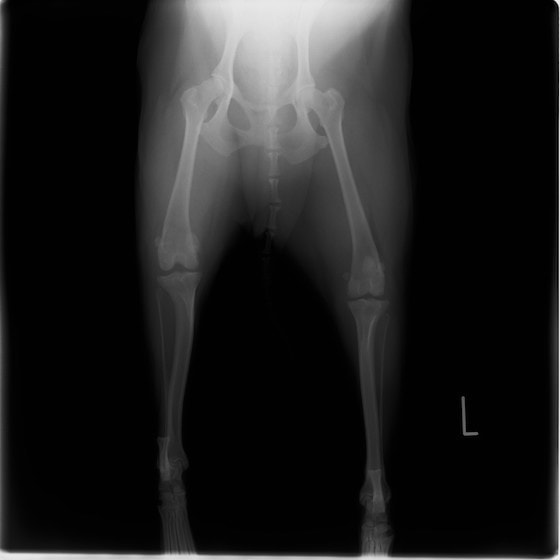

雑種 5歳

左後肢の挙上を主訴に来院されました。触診にて両関節の前方引き出し兆候、両膝蓋骨の内方脱臼を認めました。関節液検査より免疫介在性多発性関節炎は否定的でした。レントゲン検査にてfat pad signを伴う関節炎が認められたことから、前十字靭帯断裂と膝蓋骨内方脱臼(左GradeⅢ 右GradeⅢ〜IV)併発と診断し、手術を行いました。

手術は片足ずつ行い、両膝とも術中の関節鏡検査にて前十字靭帯の完全断裂と半月板損傷を確認しました。TPLO、半月板切除と滑車溝形成を始めとした膝蓋骨脱臼整復術を実施いたしました。膝蓋骨の安定化を測るために外側支帯を強固に縫合し、内側支帯は切除し縫合せずに開放状態にしています。

術前正面像

術前のTPAは左後肢33.1°右後肢26.8°でしたがTPLO実施により左後肢5.5°右後肢12°に矯正されました。